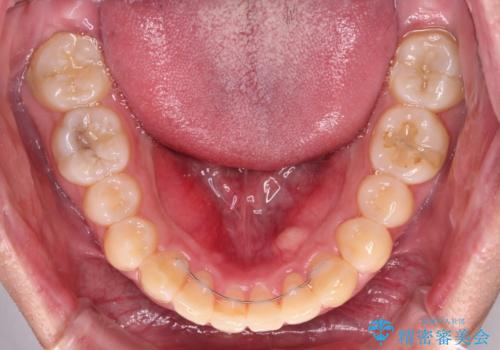

写真より左側臼歯の咬合がタイトではないことが分かりますが、こちらは保定期間に徐々に咬合させていくこととしました。